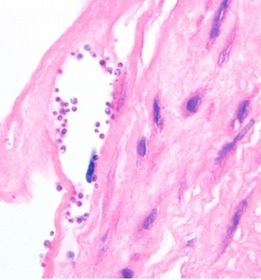

| Malassezia furfur | |

| Malassezia furfur "Spaghetti and meatballs" | |

| Malassezia furfur Clinical Man. | Tinea (Pityriasis) Versicolor _Hypo/Hyperpigmented macules on upper body usually Asymptomatic otherwise – rare pruritis Occasionally TPN (Total Parenteral Nutrition)-related sepsis _Lipids in TPN promote growth of yeast |

| Malassezia furfur Treatment | Topical azoles Selenium sulfide |